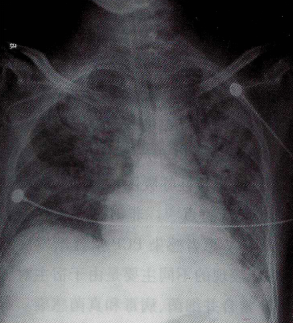

2月19日痰培养结果示:肺炎克雷伯菌,对亚胺培南、美罗培南、头孢哌酮舒巴坦、左氧氟沙星、米诺环素等敏感。当日复查床旁胸片示向心性弥漫扩散的实变影图3,较前略有好转;肺泡灌洗液吉姆萨染色回报肺孢子菌,PJP PCR阳性。抗感染方案调整为头孢哌酮舒巴坦+卡泊芬净+复方磺胺甲噁唑(每次3片,q6h)。甲泼尼龙40 mg静脉滴注bid。

图3 2016年2月19日胸部X线片:向心性弥漫扩散的实变影